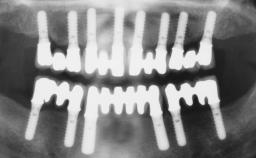

Immediate Loading of Four Implants in the Mandible and Six Implants in the Maxilla and Final Restoration with a Full-Arch Metal Framework FDP and a Full-Arch CAD/CAM Zirconia Framework FDP

A 65-year-old female patient with a failing residual maxillary dentition and a complete mandibular removable denture was referred for consultation and treatment. The patient’s chief complaint was that her upper residual teeth were mobile and she was unable to chew. The patient also asked us to improve the esthetic appearance of her smile. The patient’s desire was a stable and comfortable dentition in both jaws, and she specifically asked for a fixed rehabilitation. The patient reported a history of recurrent caries, endodontic complications, and periodontal disease as main reasons for previous teeth extractions. The anamnesis was negative for bruxism and TMJ disorders. The patient had no systemic diseases, was not on any medication,and did not smoke. The extraoral examination revealed a medium lip line, a wide diastema between the two central incisors (which, according to the patient, had appeared recently), and a partial collapse of the perioral soft tissues, probably due to loss of the correct vertical dimensions.